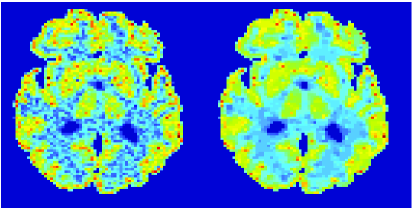

In the images shown in the figures we illustrate the calculated uptake rates of the FDG. Images for the CMRGlc can be obtained by directly scaling . In figure 1 we compare the result of using Patlak and TV-Patlak for estimating the uptake rates with respect to no noise, noise in the input function, Poisson noise in the sinogram, and finally with respect to the case in which the irreversibility assumption is violated but without noise in the sinogram or input data. In each case the histogram of the relative errors is given on the left, the Patlak image in the middle and the TV-Patlak on the right. The different scales in the histograms are due to the total number of results illustrated. When there is no noise (triples and ) the histogram illustrates results over all voxels but only one simulation, while for the noisy simulations the results are for all voxels over all realizations of the noise. The TV-Patlak images are more homogeneous in all cases and the relative errors are smaller. The figures clearly show the improvements of employing the TV-Patlak method as compared to using Patlak independently for each voxel. This is confirmed in figure 2 in which images with noise in the sinogram, positive and different noise levels in the input function are shown.

In figures 3 and 4 we illustrate the uptake rates and relative error in the uptake rates, respectively, calculated by Patlak, TV-Patlak, Patlak-GF and Patlak-MF for one simulated data case , i.e. , noise in the input function and Poisson noise in the sinograms. The uptake rate image generated by Patlak-MF is visually smoother than that by TV-Patlak, but the equivalent histograms show that the relative error is higher for Patlak-MF than for TV-Patlak; the Patlak-MF image is over-smoothed.